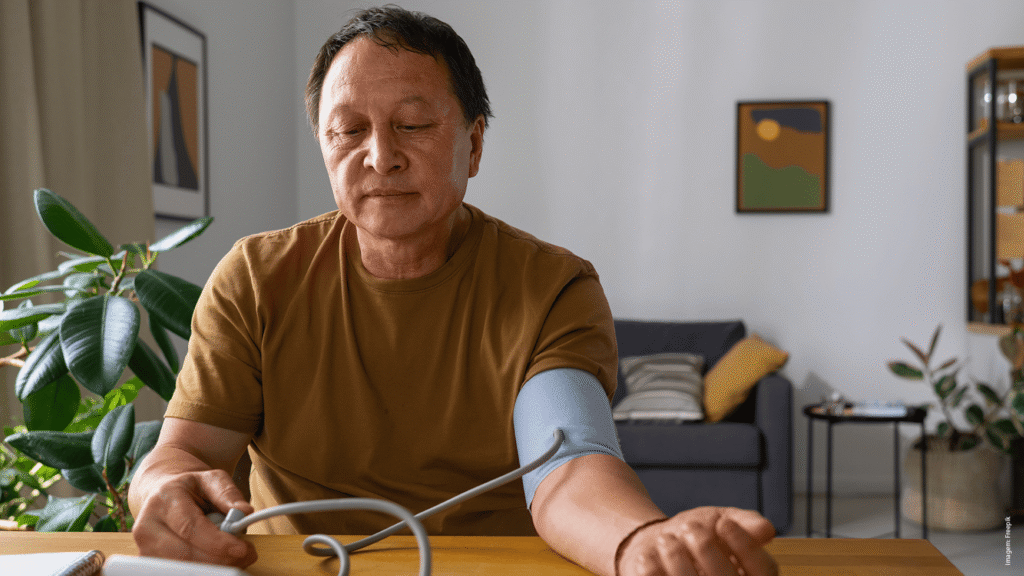

Muitas pessoas não buscam tratamento adequado e sofrem em silêncio, mas especialista afirma que o tratamento é muito eficaz